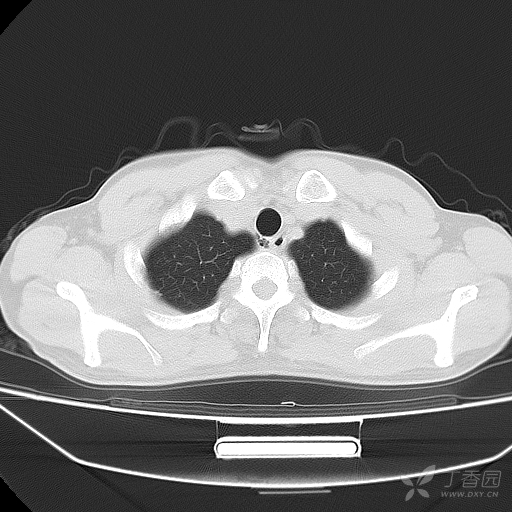

【共享】气管憩室一例!